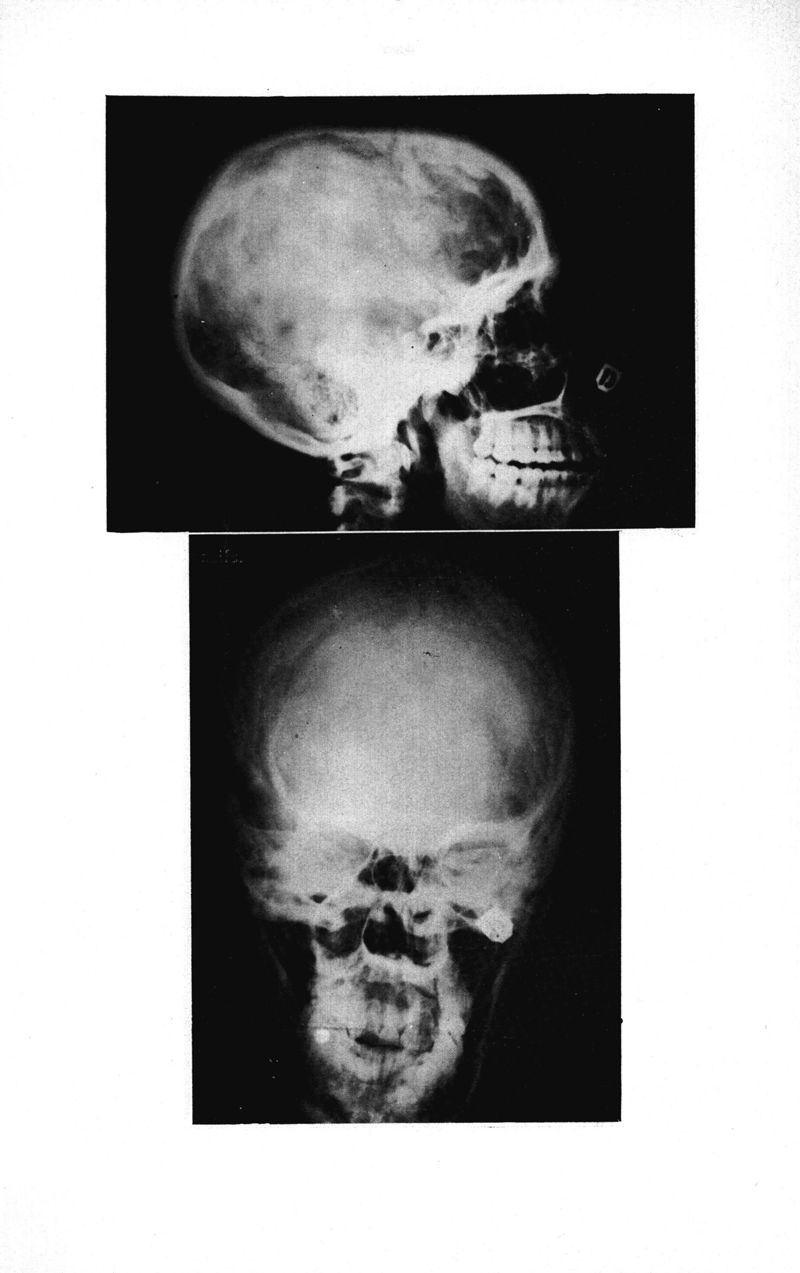

Médecine tropicale: revue française de pathologie et de santé publique tropicales

. - Marseille, 1974.